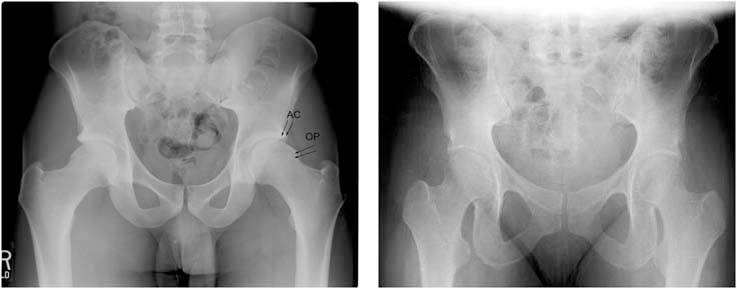

1.These are two radiographs showing the patient's pelvis (left) compared to an a normal pelvis (right). His radiograph reveals a mushroom shaped femoral head with an abnormal contour or osteophyte (OP) which is a classic finding in CAM impingement. The edge of the hip socket (the acetabulum) also has some early arthritis shown by increased bone density at the upper edge (AC).